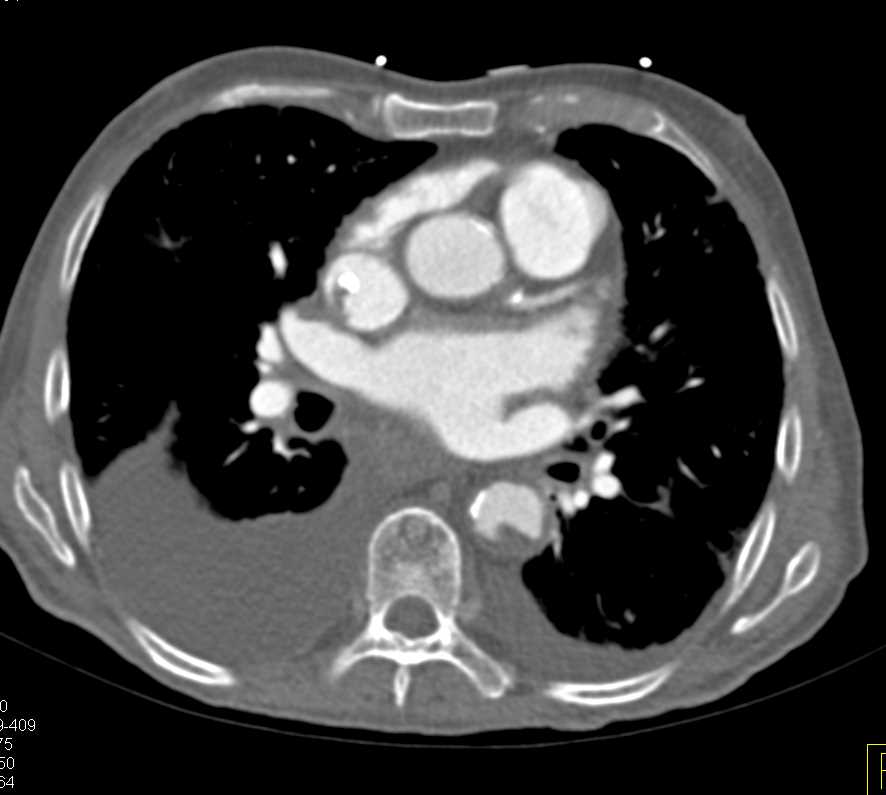

Type 3 Endoleak Thoracic Aorta with Endovascular Stent